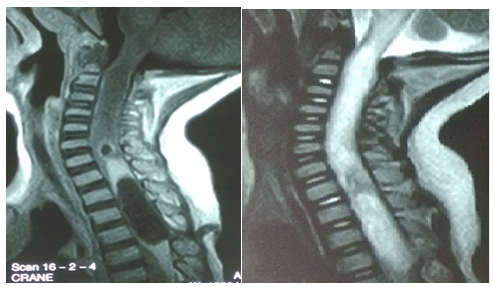

It is a 15-month-old infant of Mauritanian nationality, with a history of unprotected neonatal infection, received in our neurological clinic for motor deficiency of the two lower limbs. His psychomotor development was normal. The symptomatology evolved for about 4months, with the occurrence of a fever, irritability and a dorsal kyphosis. In view of these manifestations, the infant was brought to the local health center for treatment, where a non-documented treatment has been instituted for a period of 10days. After 10days of treatment, the patient presented progressively over 20days a motor deficit of the lower limbs preceded by a functional impotence of the lower limbs causing an impossibility of the walking and the seated station, without context of acute retention of urine or constipation. This is what motivated the parents to consult again in another health center in Nouakchott where the patient was hospitalized for 5days and left without improvement of his clinical picture. Finally, he will be referred to the FANN Neurology Clinic in Dakar for specialized care. It should be noted that the parents of the infant had detected a dorsal cutaneous swelling during his neonatal period, but they had thought that it was an innocent lesion that did not need further investigation (of little clinical importance). The clinical examination found a good state of hydration, hyperthermia at 38.5°C. The infant was conscious with good preservation of superior functions. However, he had a spastic paraplegia with a muscular force rated at 0/5 on the two lower limbs, osteo-tendinous reflexes were sharp at the two lower limbs, poly kinetic and diffuse with an epileptoid trepidation of the feet, plantar reflexes were in extension, the neck was supple. On the other hand, tone, muscle strength and osteo-tendinous reflex were normal to the upper limbs. There were no signs of meningeal irritation. At the level of the musculoskeletal system, a kyphosis of the dorsal spine was noted with a slight hyper chromic swelling surrounded by a pilosity with respect to the T3-T4 dermatomes, suggesting a dermal sinus (Figure 1). The rest of the clinical examination was normal. The hypotheses of a compressive or non-compressive myelopathy associated with dysraphia were mentioned. The medullar MRI performed showed an edema of the cervico-dorsal marrow as well as the bulbar junction, with lesional signal abnormality, hypo-intense T1, hyper-intense T2, heterogeneous enhancement, with a small area In a cockade with a hypo-intense center at the height of C6-C7, a part strongly raised facing T1 and a fusi form part of 31x11,8mm just below. A linear fistula was seen, communicating the collected lesion to the skin (Figure 2). The diagnosis of intramedullary abscess was retained. The haematological assessment found a leukocytosis at 19000/mm3 and the sedimentation rate was high. A neurosurgical procedure was performed and confirmed the existence of the dermal sinus, communicating the skin to the medullary space through a cord (Figure 3). Partial Laminectomy was performed with drainage and lavage of the cavity (Figure 4), but also a resection of the sinus. The cytobacteriological examination of pus isolated Staphylococcus aureus. Prior to pus culture, treatment consisted of broad spectrum antibiotic therapy with Ceftriaxone, Metronidazole and Gentamycin. And after the isolation of the germ, the infant was put on Vancomycin and Chloramphenicol. Evolution was satisfactory with partial recovery of muscle strength.

Figure 1 An abnormality of lesional signal, hypo-intense in T1, hyper-intense in T2, with a small zone in cockade with a hypo-intense center at the height of C6-C7, a part strongly enhanced opposite T1, a fusiform part 31x11, 8 mm just below. A linear fistula was seen causing the collected lesion to communicate with the skin.